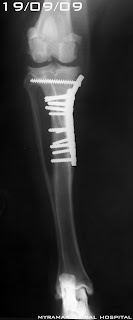

Fractura diafisaria tranversa simple tibial izquierda. Clas. AOVET:41-A3

La tibia se reduce y estabiliza utilizando placa DCP 2.7mm + 8 tornillos 2.7mm.

Se presenta evolución radiográfica del caso